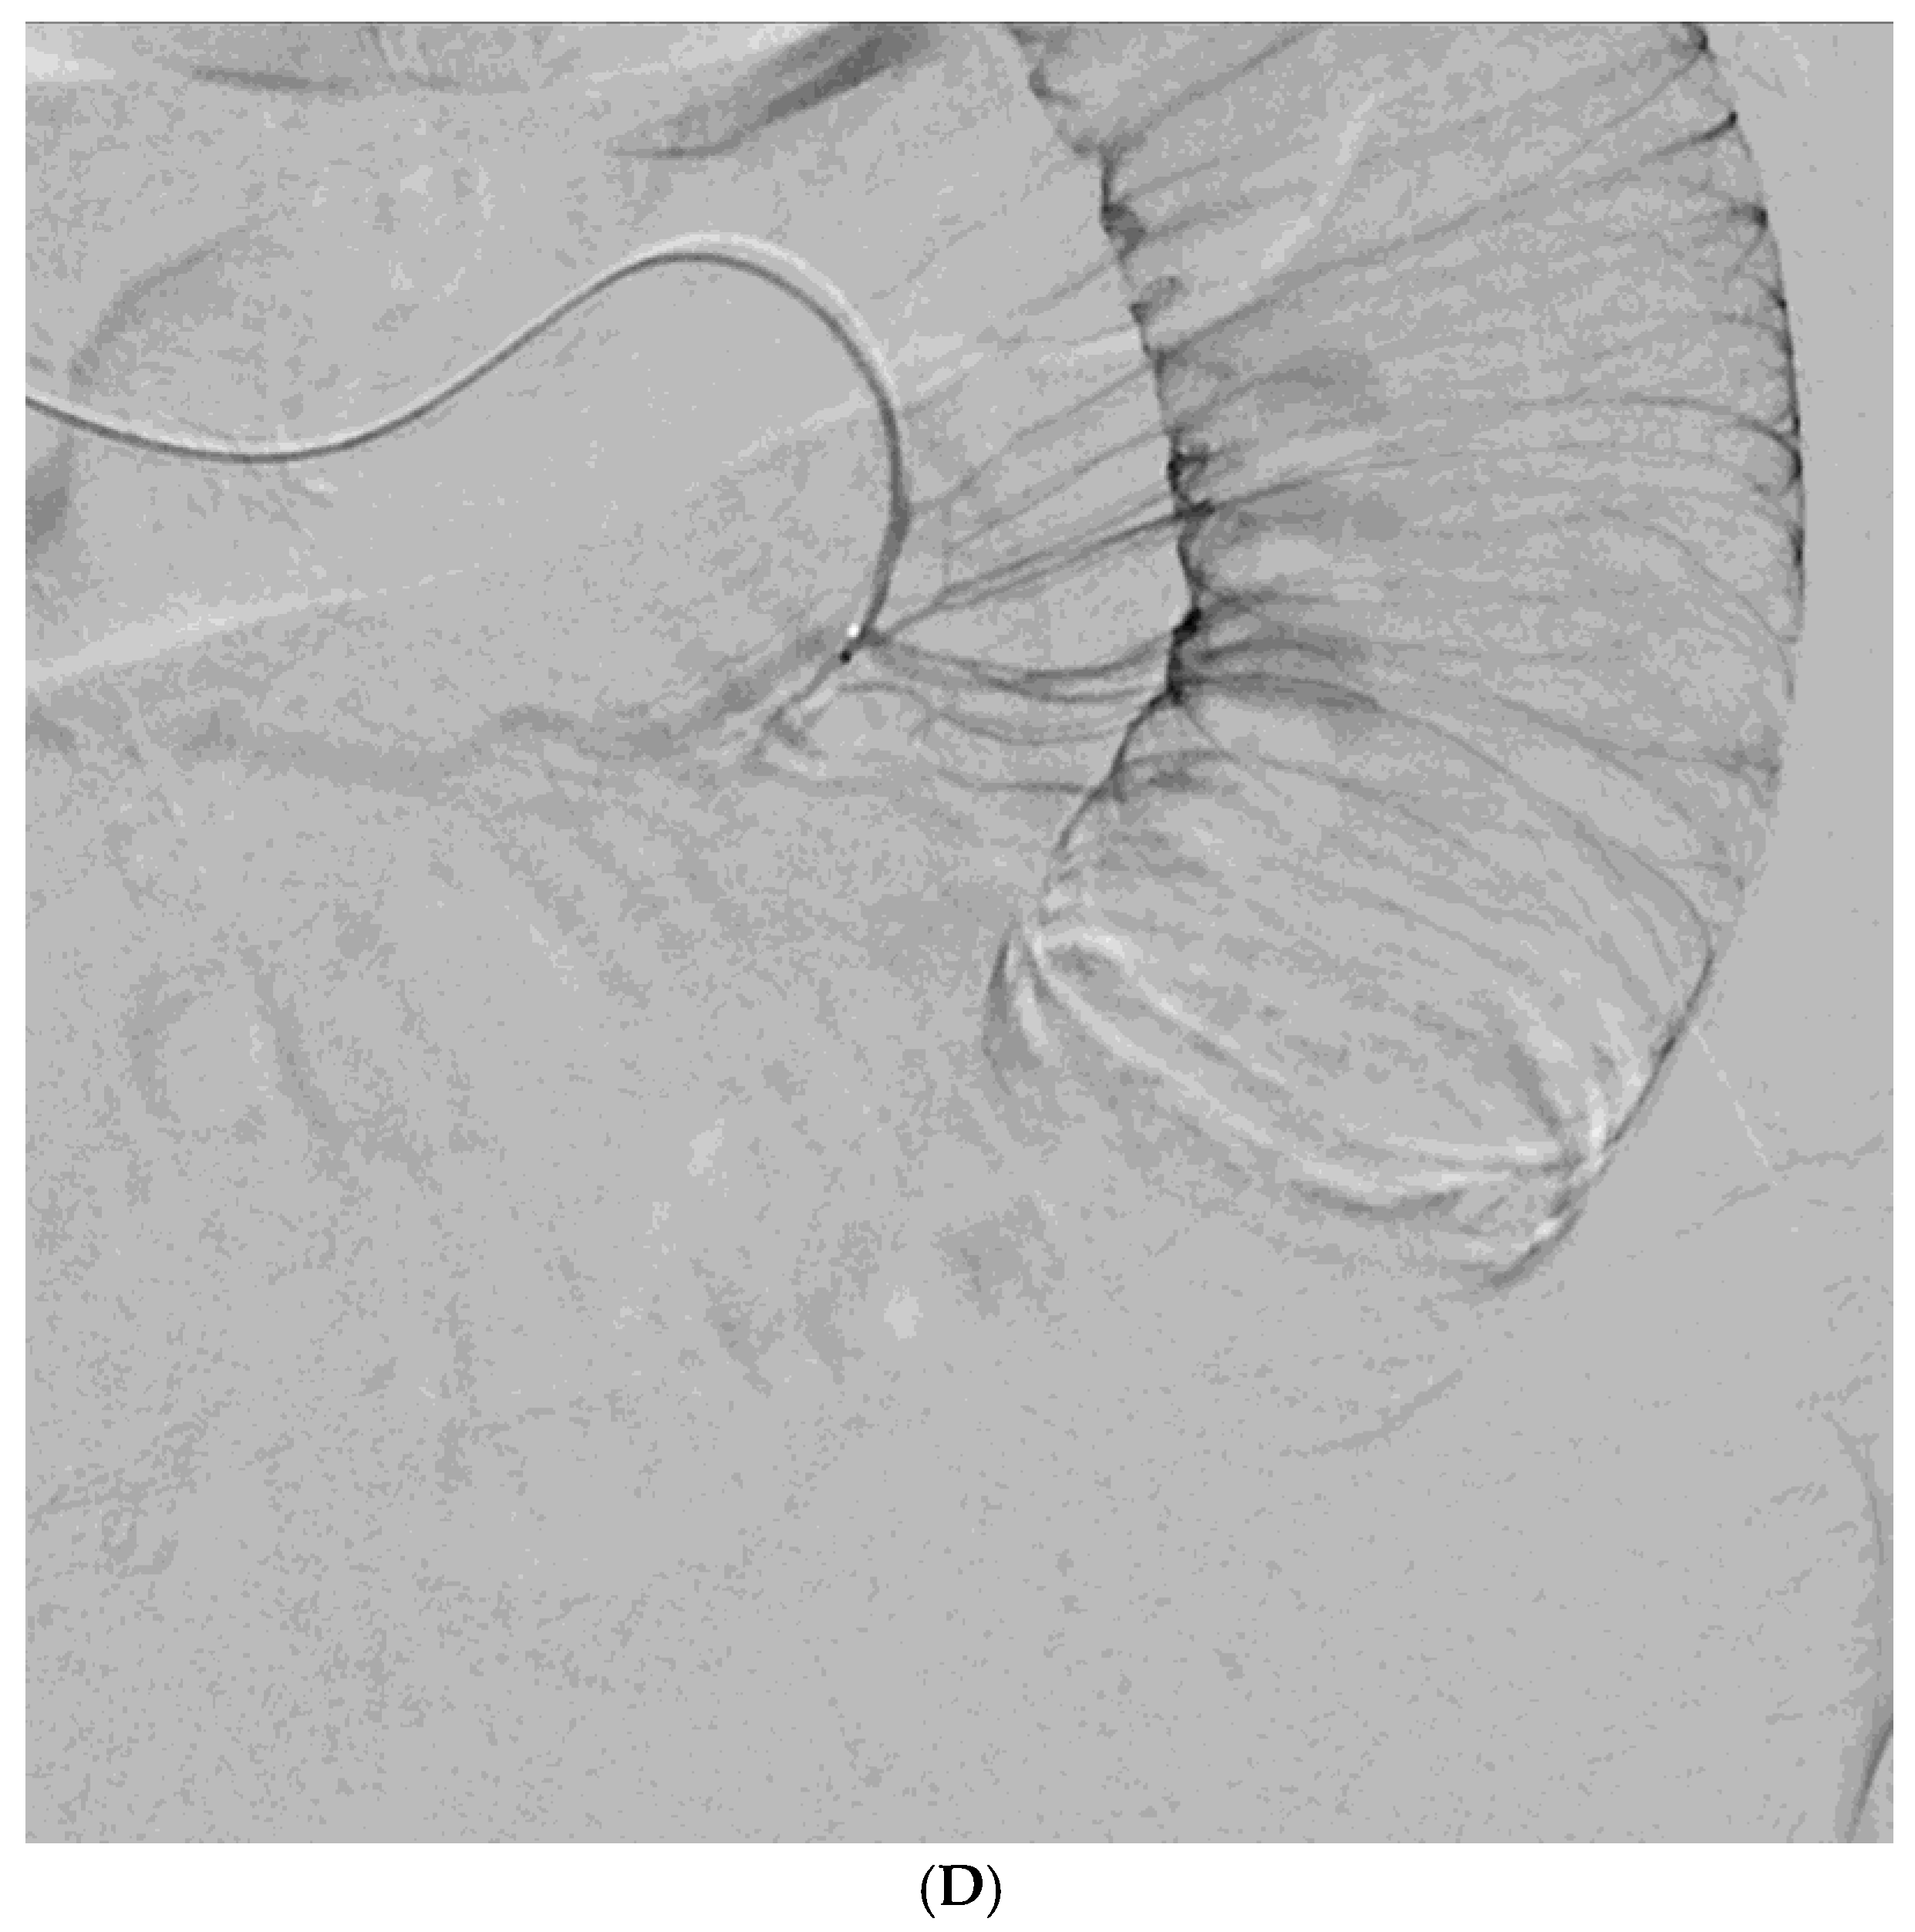

Figure 1. A 78-year-old man presented with hematochezia. (A) Contrast-enhanced axial CT image shows luminal contrast extravasation (arrow) at the ileal loop. (B, C) Selective ileal arteriography shows contrast extravasation (arrows). Due to the distance and tortuosity of the path from the microcatheter tip (arrowheads) to the bleeding focus, superselection was not possible; therefore, embolization was performed using quick-soluble gelatin sponge particles (350–560 µm). (D) Post-embolization arteriography demonstrates that the bleeding focus and the arterial branches leading to it are no longer visible. No further bleeding occurred during the 1-year follow-up.